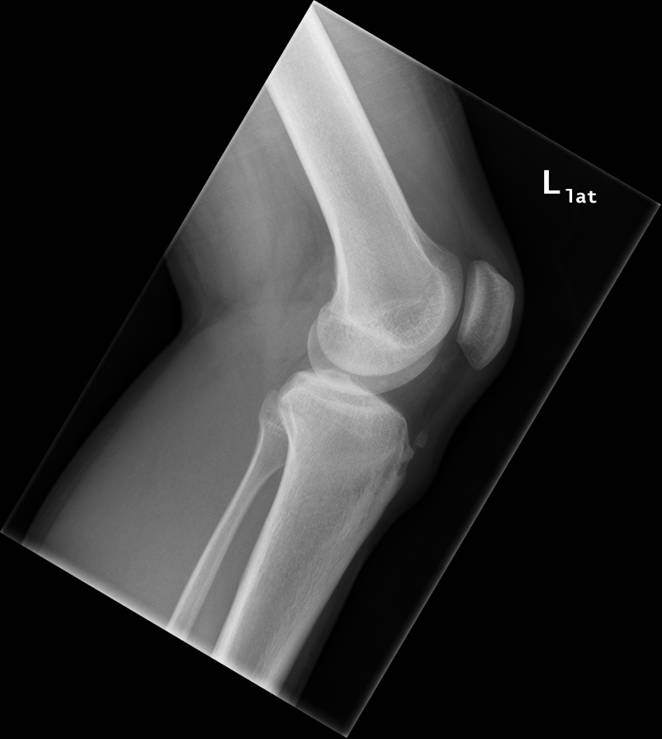

Knæ, Normal, Røntgen

Normalt røntgenbillede af venstre knæ i 2 projektioner.